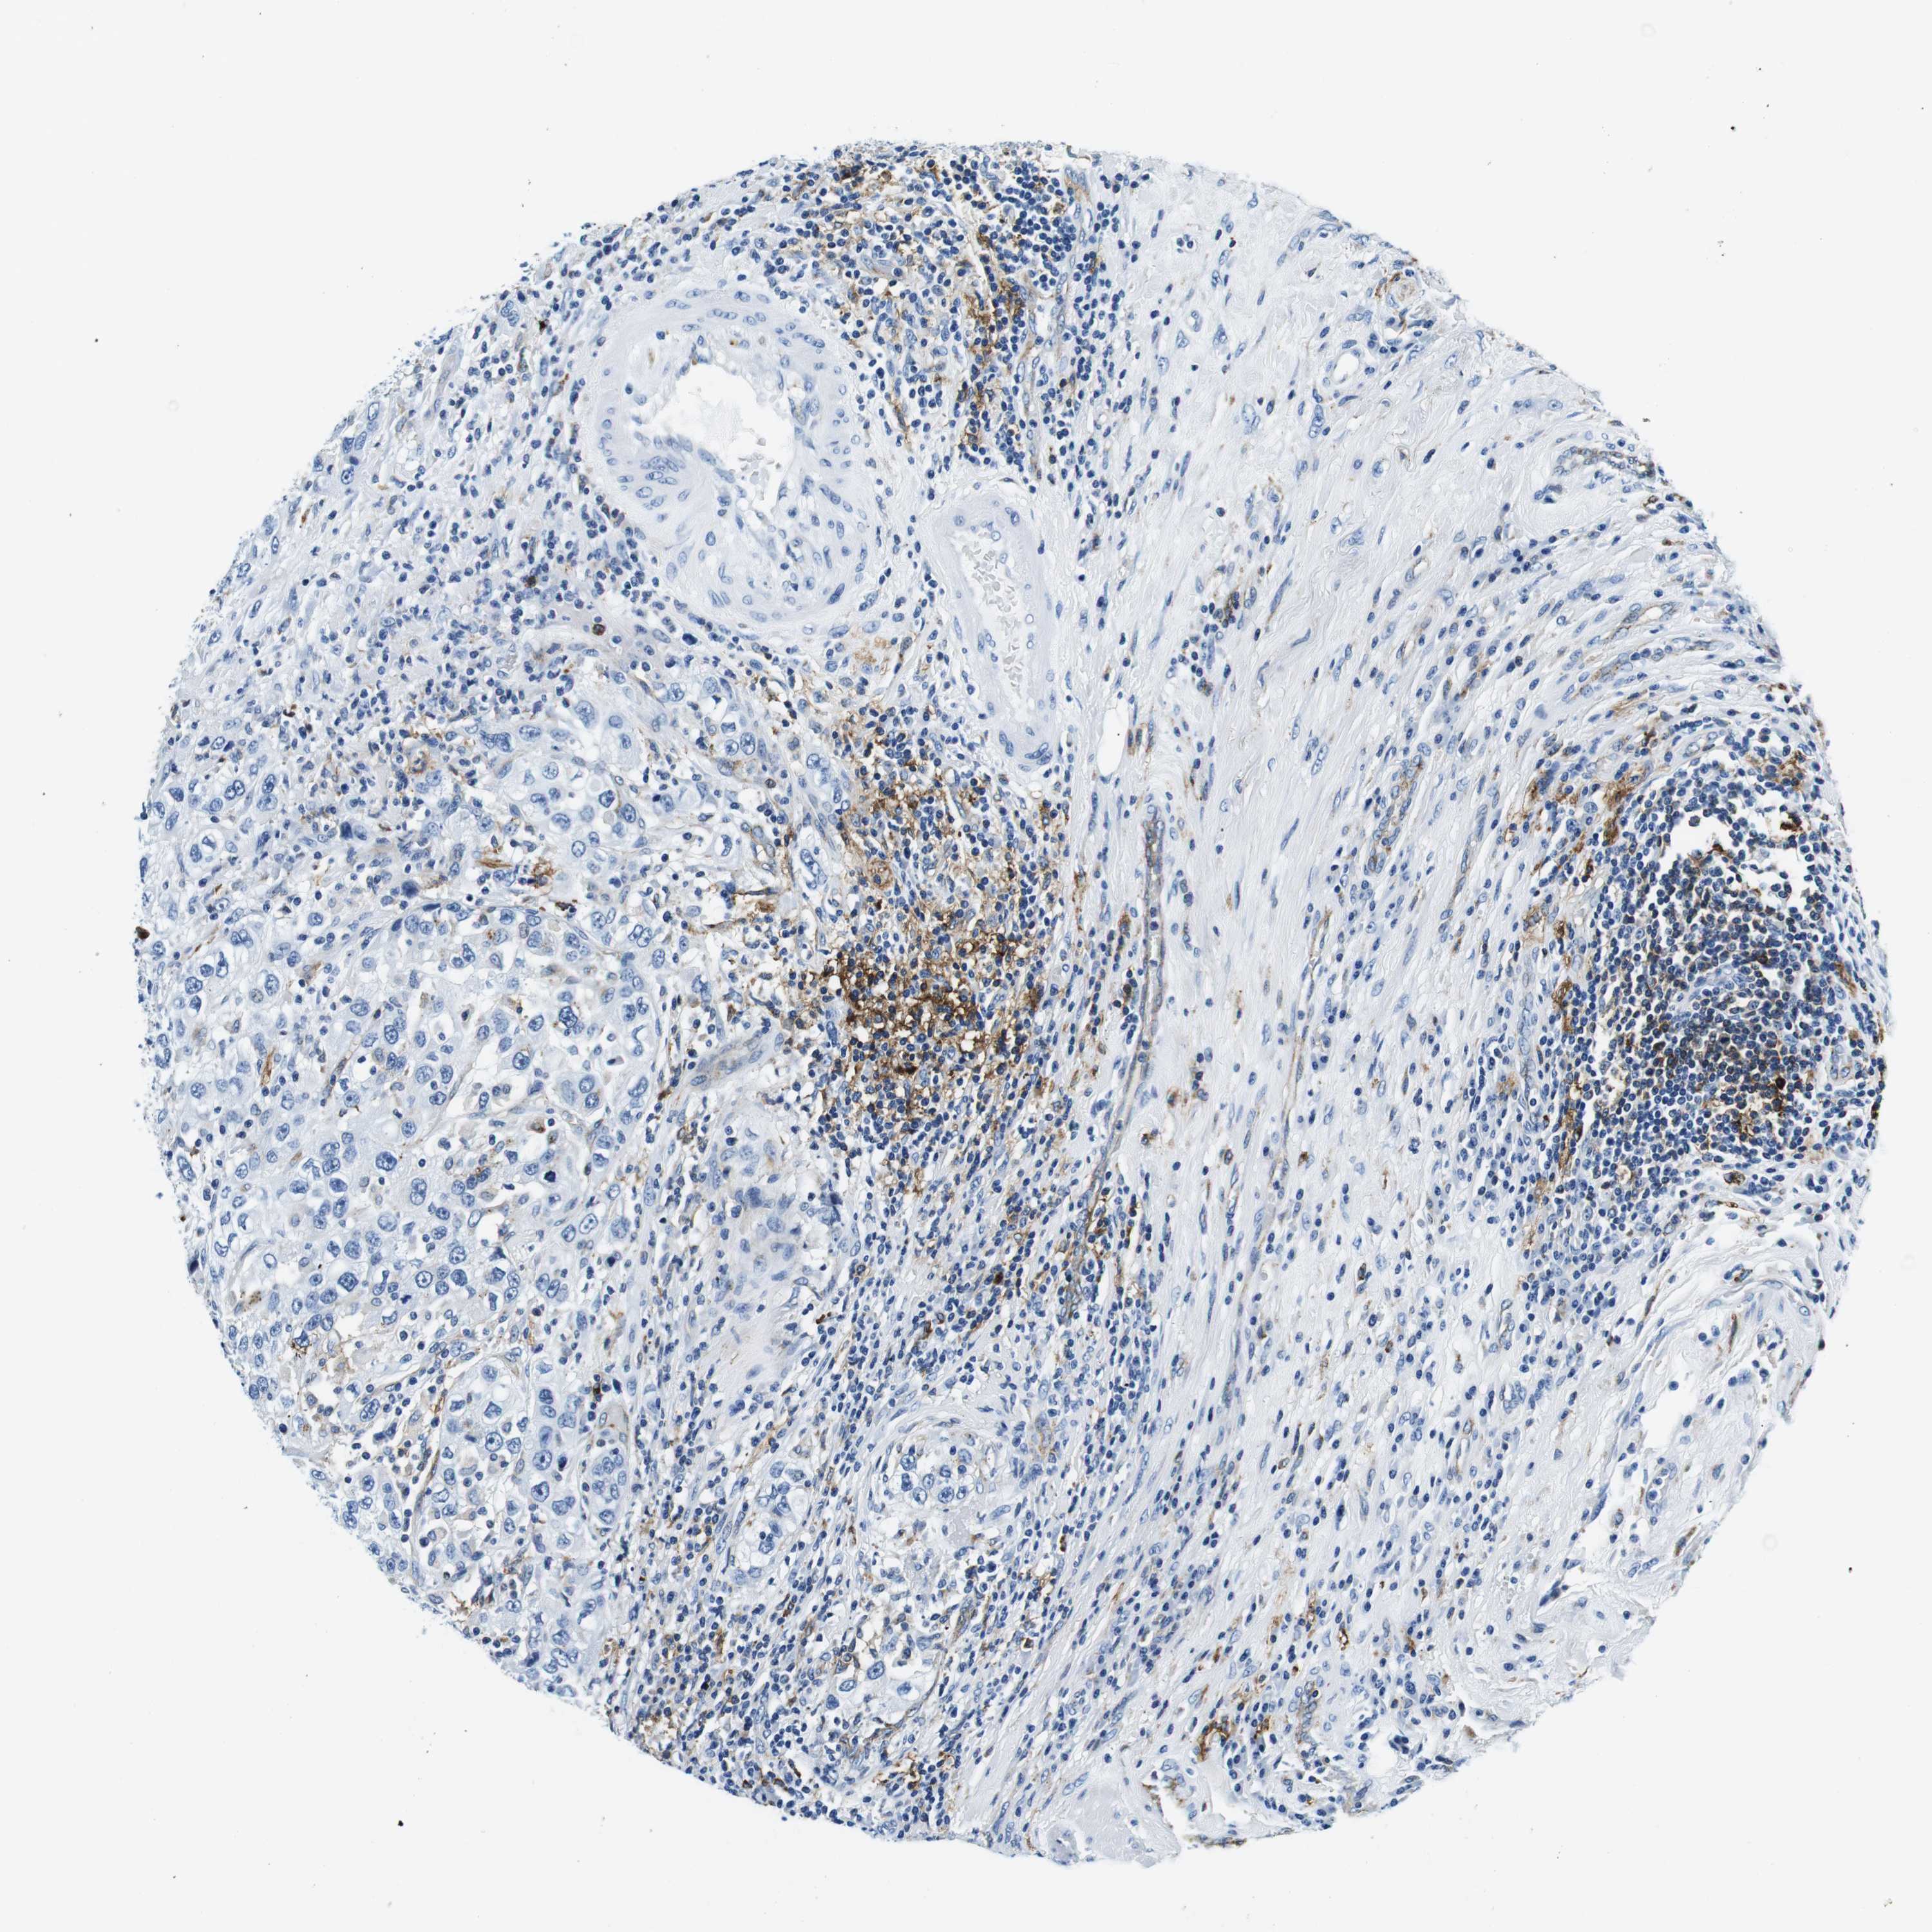

UROTHELIAL CANCER - Protein expressioni

A mouse-over function shows sample information and annotation data. Click on an image to view it in a full screen mode. Samples can be filtered based on level of antibody staining by selecting one or several of the following categories: high, medium, low and not detected. The assay and annotation is described here.

Note that samples used for immunohistochemistry by the Human Protein Atlas do not correspond to samples in the TCGA dataset.

Antibody stainingi

Antibody staining in the annotated cell types in the current human tissue is reported as not detected, low, medium, or high, based on conventional immunohistochemistry profiling in selected tissues. This score is based on the combination of the staining intensity and fraction of stained cells.

Each image is clickable and will lead to virtual microscopy that enables deeper exploration of all samples and also displays staining intensity scores, fraction scores and subcellular localization as well as patient and tissue information for each sample.

Antibody HPA043151

Antibody CAB015400

Antibody CAB034021

Urothelial carcinoma, High grade

Urothelial carcinoma, Low grade